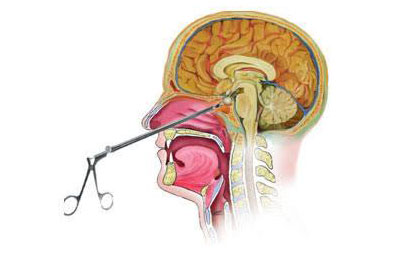

Pituitary Tumours

These are brain tumours found at the base of skull, they present with headache, visual disturbance and hormonal problems. They are diagnosed by CT or MRI brain And visual or hormonal test They are removed by surgery. We at lifeline hospital remove them endoscopically through nose, it gives faster recovery It is one of the advances in neurosurgery. Last week we removed three such large brain tumours ( pituitary), all patients doing well, with the help of government scheme, with minimal expenses.

These are mri pictures and operative video.

Dr Sandeep Inchanalkar

(Neurospinal surgeon) LIFE LINE HOSPITAL KOLHAPUR.